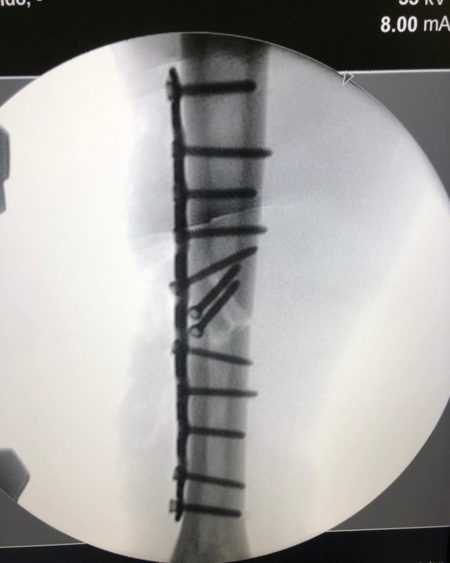

He underwent surgery led by MotoGP Traumatology Specialist Dr Xavier Mir in Barcelona on the following Tuesday, when a titanium plate was fitted to the arm, and it was thought that he was a doubtful proposition for Round 3 in the Czech Republic.

Among them are a broken limb prior to surgery and a limb with a plate and 12 screws fixed to it.